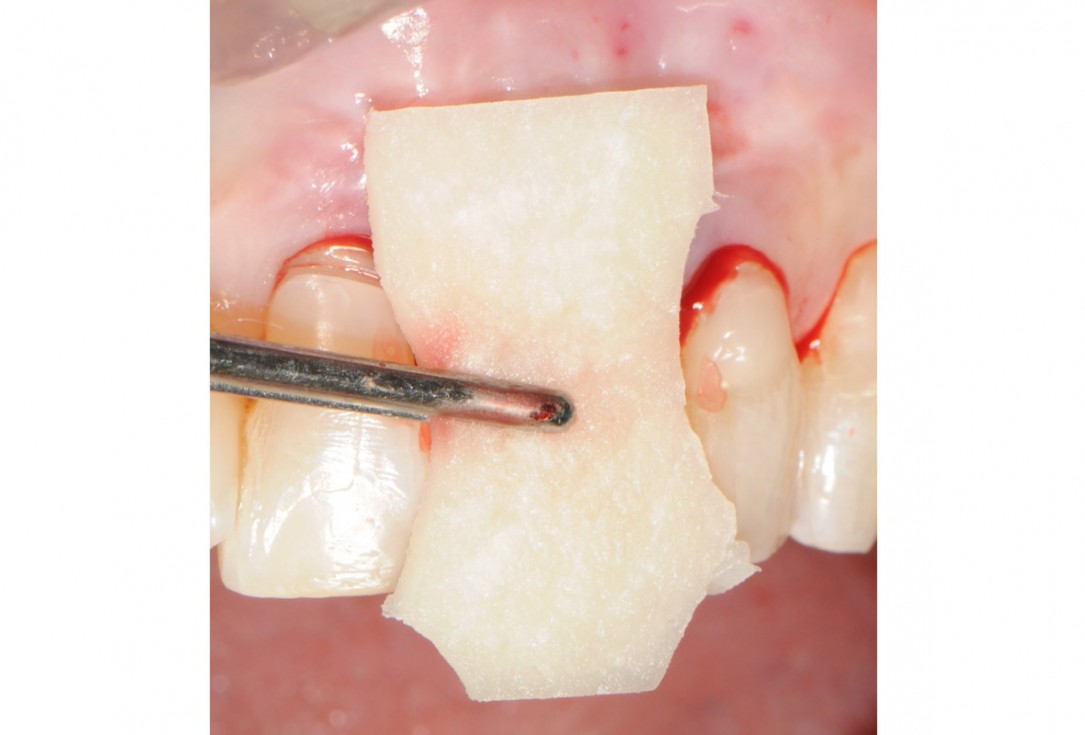

7/18 - Hydration of mucoderm® for a few minutesTooth extraction and socket sealing with mucoderm® - Dr. A. Rossi